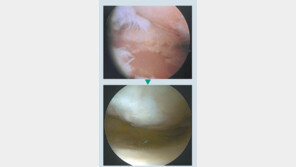

![[헬스동아]손상된 무릎 관절에 줄기세포 이식… “12개월이면 완치 ”](https://dimg.donga.com/a/296/167/95/2/wps/NEWS/IMAGE/2017/01/10/82303337.2.jpg)

#신모 씨(61)는 의자에서 앉았다 일어나는 것부터 계단을 오르내리는 것까지 일상적인 움직임이 힘들었다. 동네 정형외과와 대학병원을 다니며 치료법을 찾아봤지만 대부분 인공 관절 수술을 권유했다. 하지만 신 씨는 재수술 위험이 있는 인공 관절 수술을 선뜻하기 어려웠다. 그러다 재작년, …